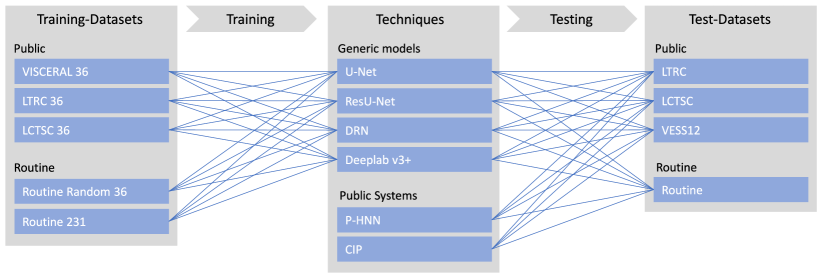

We trained four generic semantic segmentation models from scratch on three different public training sets and one training set collected from the clinical routine. We evaluated these models on public test sets and routine data, including cases showing severe pathologies. Furthermore, we performed a comparison of models trained on a diverse routine training set to two published automatic lung segmentation systems, which we did not train, but used as provided. An overview of training and testing performed is given in Fig. 1.